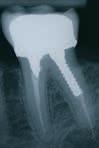

B.

C. CBCT (sagittalt og koronalt aspekt), der viser en rodfyldt +6 med lille apikal radiolucens (pile). Ved rodfyldte tænder overestimerer CBCT ofte forekomsten af apikal parodontitis, og fundene skal derfor vurderes kritisk. (Kruse et al., 2019).